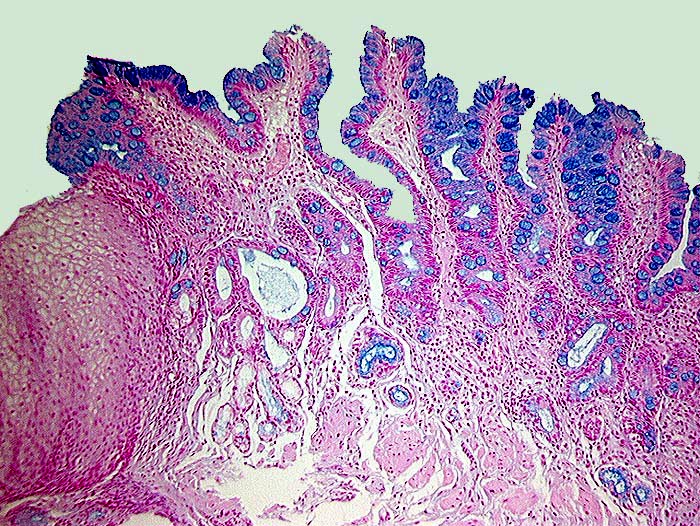

Barrett Schleimhaut ohne intraepitheliale Neoplasie

Metaplasie / Heterotopie

Oesophagogastrischer Uebergang

Oesophagus, Magen

Zwischen erhaltenen Inseln normaler Ösophagusschleimhaut findet sich spezialisiertes metaplastisches Epithel mit alcianblauen Becherzellen.

Endobrachyösophagus

Histologie